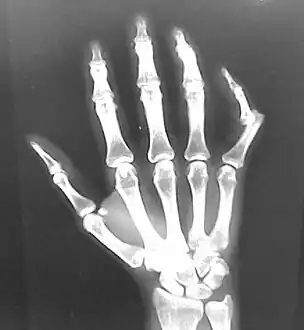

Dislocation of the carpo-metacarpal joint.